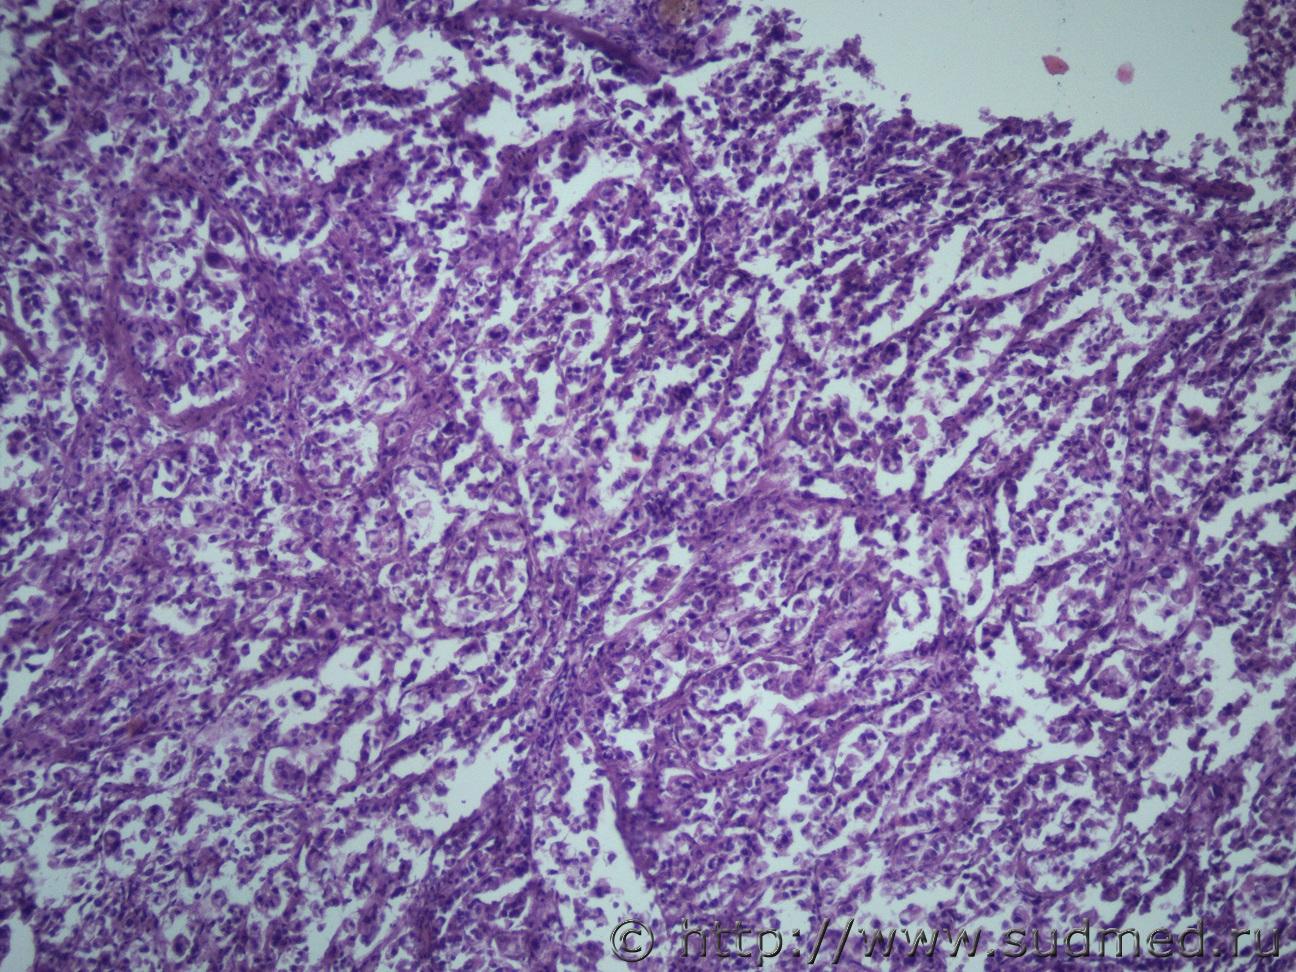

Ув. коллеги нужна помощь. Муж 60 лет. Эксперт присылает злокачественное новообразование левой почки с метастазами в правую почку и легкие. В стеклах опухоль в почке над капсулой (какая это почка правая или левая не указано) Судебная медицина - Прикрепленное изображение Судебная медицина - Прикрепленное изображениеСудебная медицина - Прикрепленное изображениеСудебная медицина - Прикрепленное изображениеСудебная медицина - Прикрепленное изображение

По мне - железистый вариант гипернефроидного рака.

Гипернефроидный рак.

Почечно медуллярная карцинома с mts в легкие